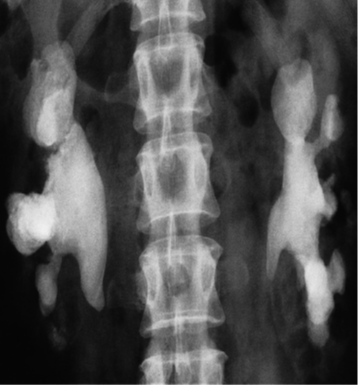

(a) IVU control film. Renal stones are not visible on the right and are very poorly visualized on the left. (b) IVU following intravenous contrast. Filling defects are seen in the right lower calix and pelvis and in the left upper pole calices . (c, d) CT of the kidneys in the same patient with no contrast medium, reformatted in the coronal plane, demonstrating the renal stones in both the right (c) and left (d) kidneys.